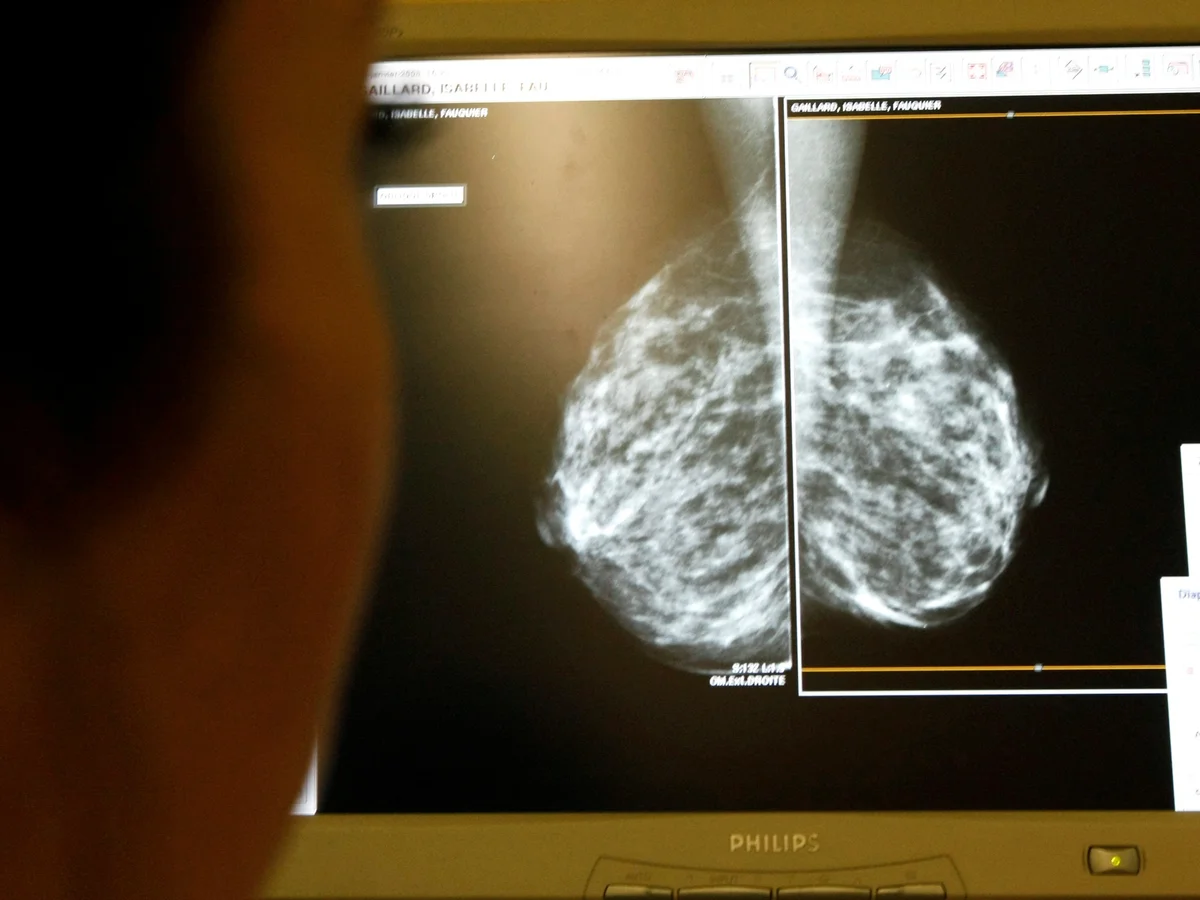

At the heart of the research was a sophisticated AI tool designed to analyse mammogram images before human review. The system categorised scans into risk levels, assigning low-risk images to a single radiologist and directing high-risk cases for double reading. Suspicious areas were highlighted to draw clinical attention, enabling radiologists to focus their expertise where it mattered most. This approach aimed to maintain safety while easing workload pressures in overstretched screening services.

Results published in The Lancet revealed that mammography supported by artificial intelligence led to a 12% reduction in cancer diagnoses during the years following screening. In numerical terms, 1.55 cancers were diagnosed per 1,000 women in the AI-supported group, compared with 1.76 per 1,000 in the standard screening group. Researchers interpret this difference as evidence that more cancers were identified earlier, reducing the number emerging later at more advanced stages.

Early detection is a critical factor in breast cancer outcomes, and the study demonstrated clear progress in this area. More than 81% of cancers in the AI-supported group were detected during routine screening appointments. By contrast, just under 74% were identified at the screening stage in the control group. This improvement suggests that AI breast screening can help identify tumours before symptoms develop, when treatment options are often less invasive and more effective.